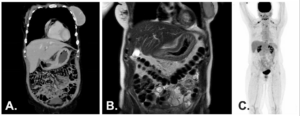

Thoracic and abdominopelvic CT, as well as abdominal magnetic resonance imaging MRI, showed diffuse thickening of the gastric wall without evidence of distant metastatic disease. Whole-body PET-CT (FDG) did not reveal any abnormal radiotracer uptake.

Figure 2. A – Thoracic and abdominopelvic CT (coronal view). B – Abdominal MRI (T2, coronal view). C – Whole-body PET-CT (FDG).